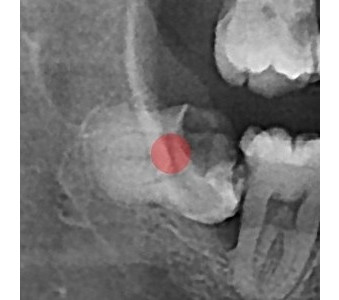

以成果证明实力。

国际摩牙齿科

真实临床案例